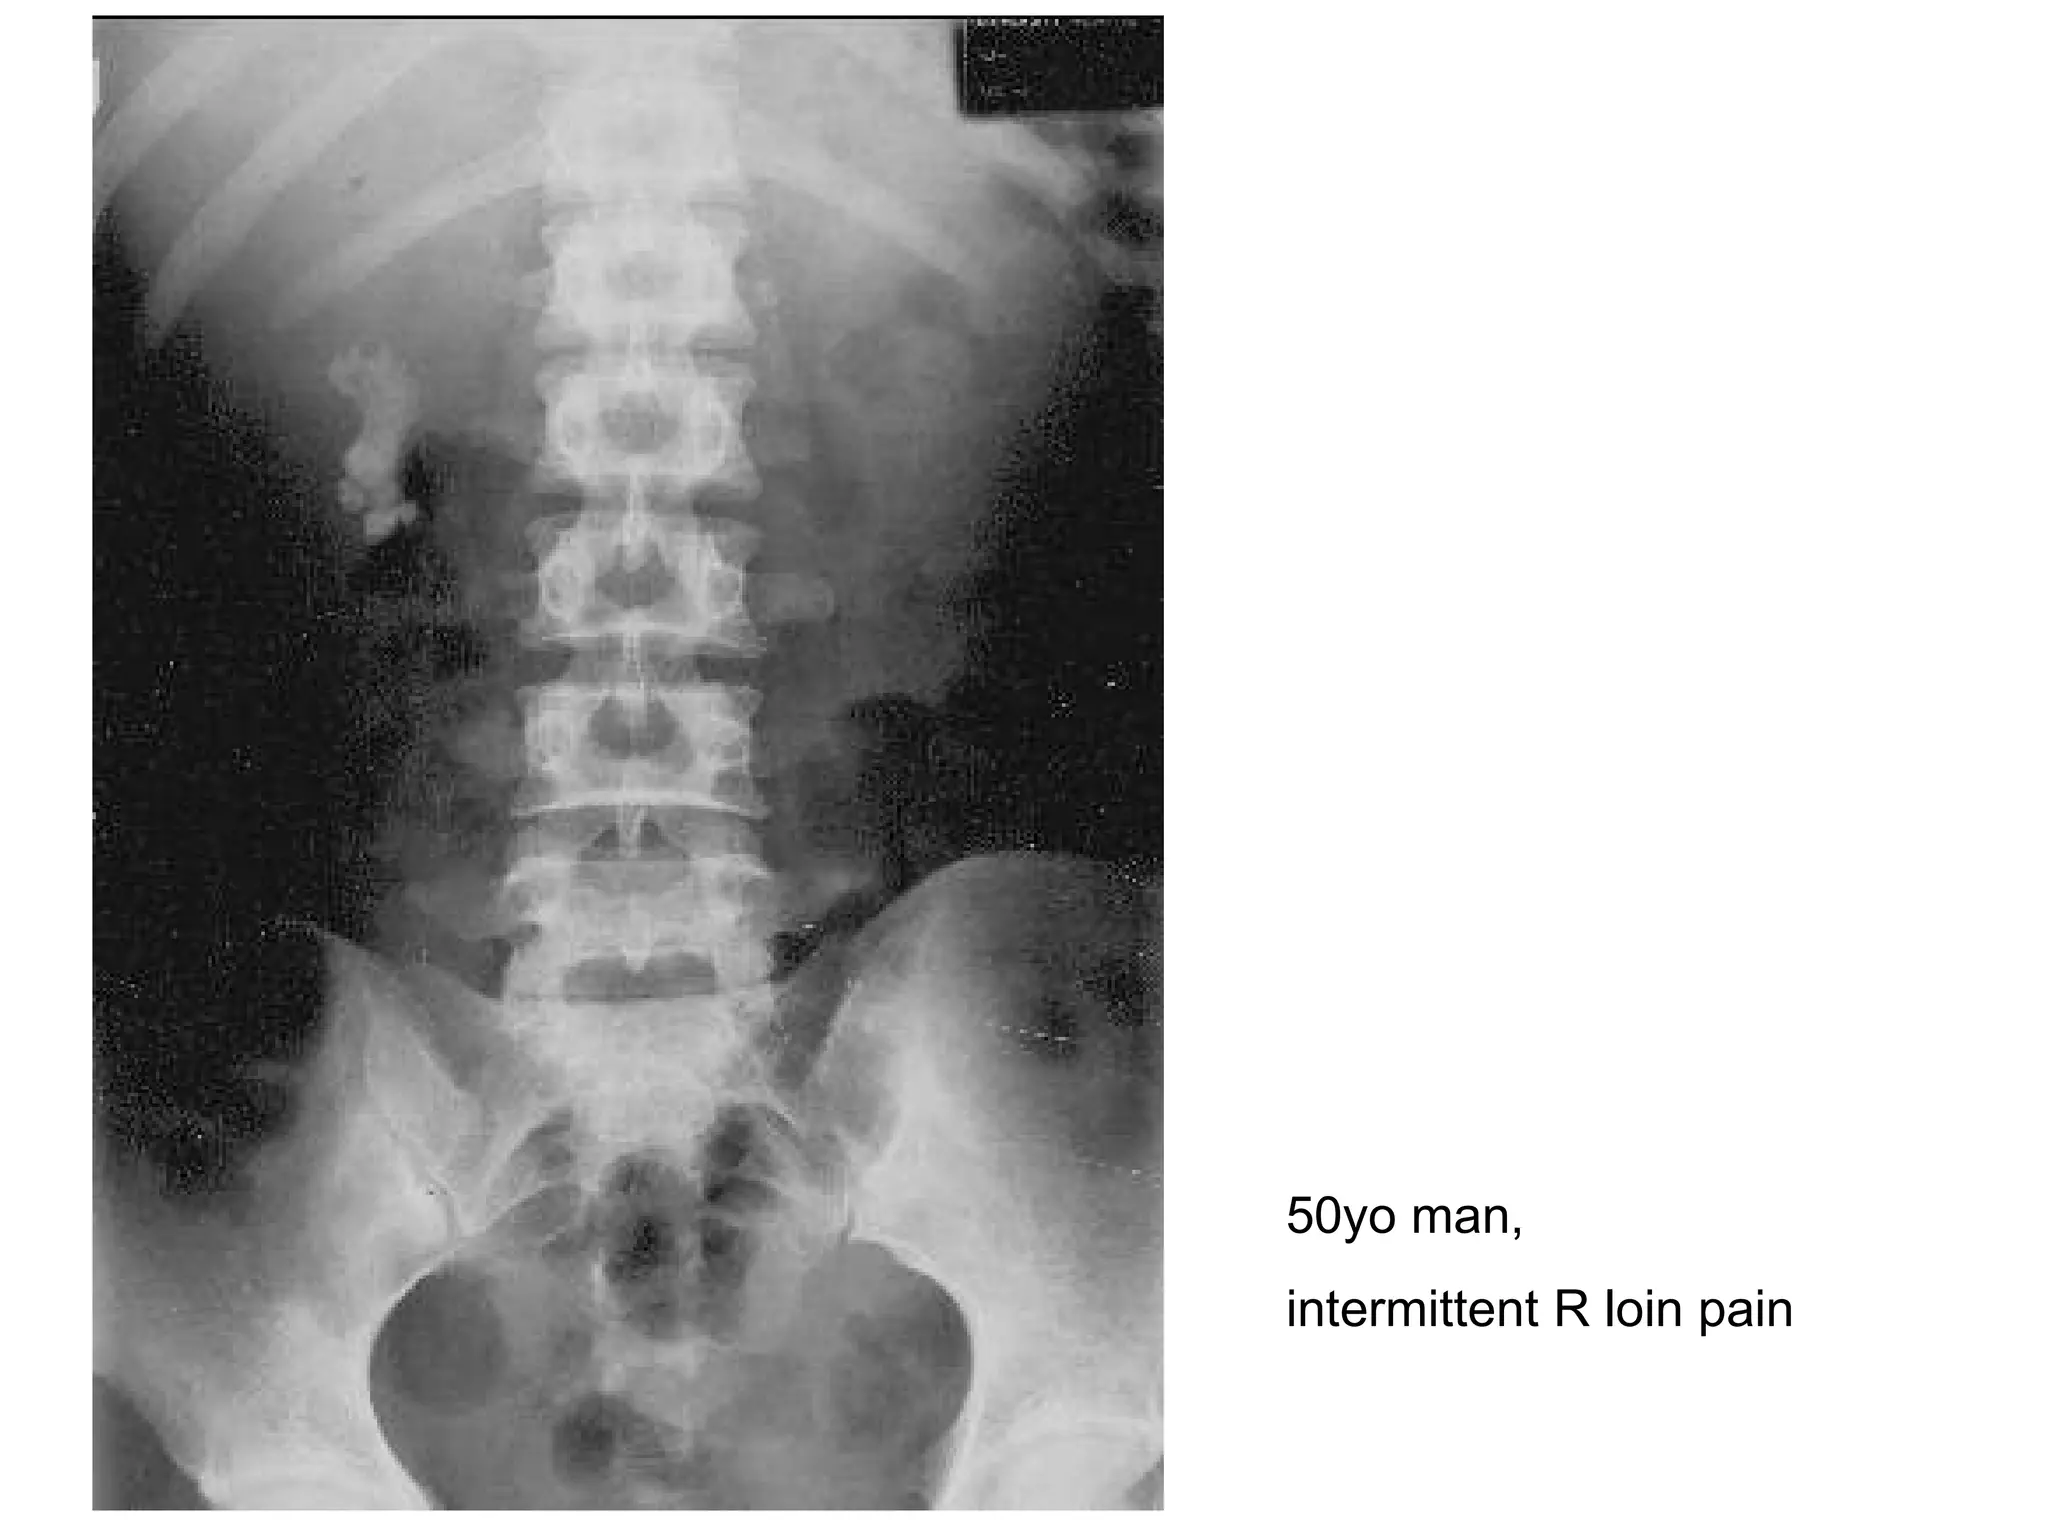

50yo man,  intermittent R loin pain

AXR/KUB- renal calculi Describe? Radio-opaque mass noted at R kidney Dx? Renal staghorn calculi Cx? Hydronephrosis/pyelo-nephrosis/-nephritis Renal failure SCC 2 other Ix? IVU (filling defect/impaired renal fx) Renal U/S (exclude hydronephrosis/hydroureter)

AXR/KUB- renal calculiDescribe? Radio-opaque mass noted at R kidney Dx? Renal staghorn calculi Cx? Hydronephrosis/pyelo-nephrosis/-nephritis Renal failure SCC 2 other Ix? IVU (filling defect/impaired renal fx) Renal U/S (exclude hydronephrosis/hydroureter)